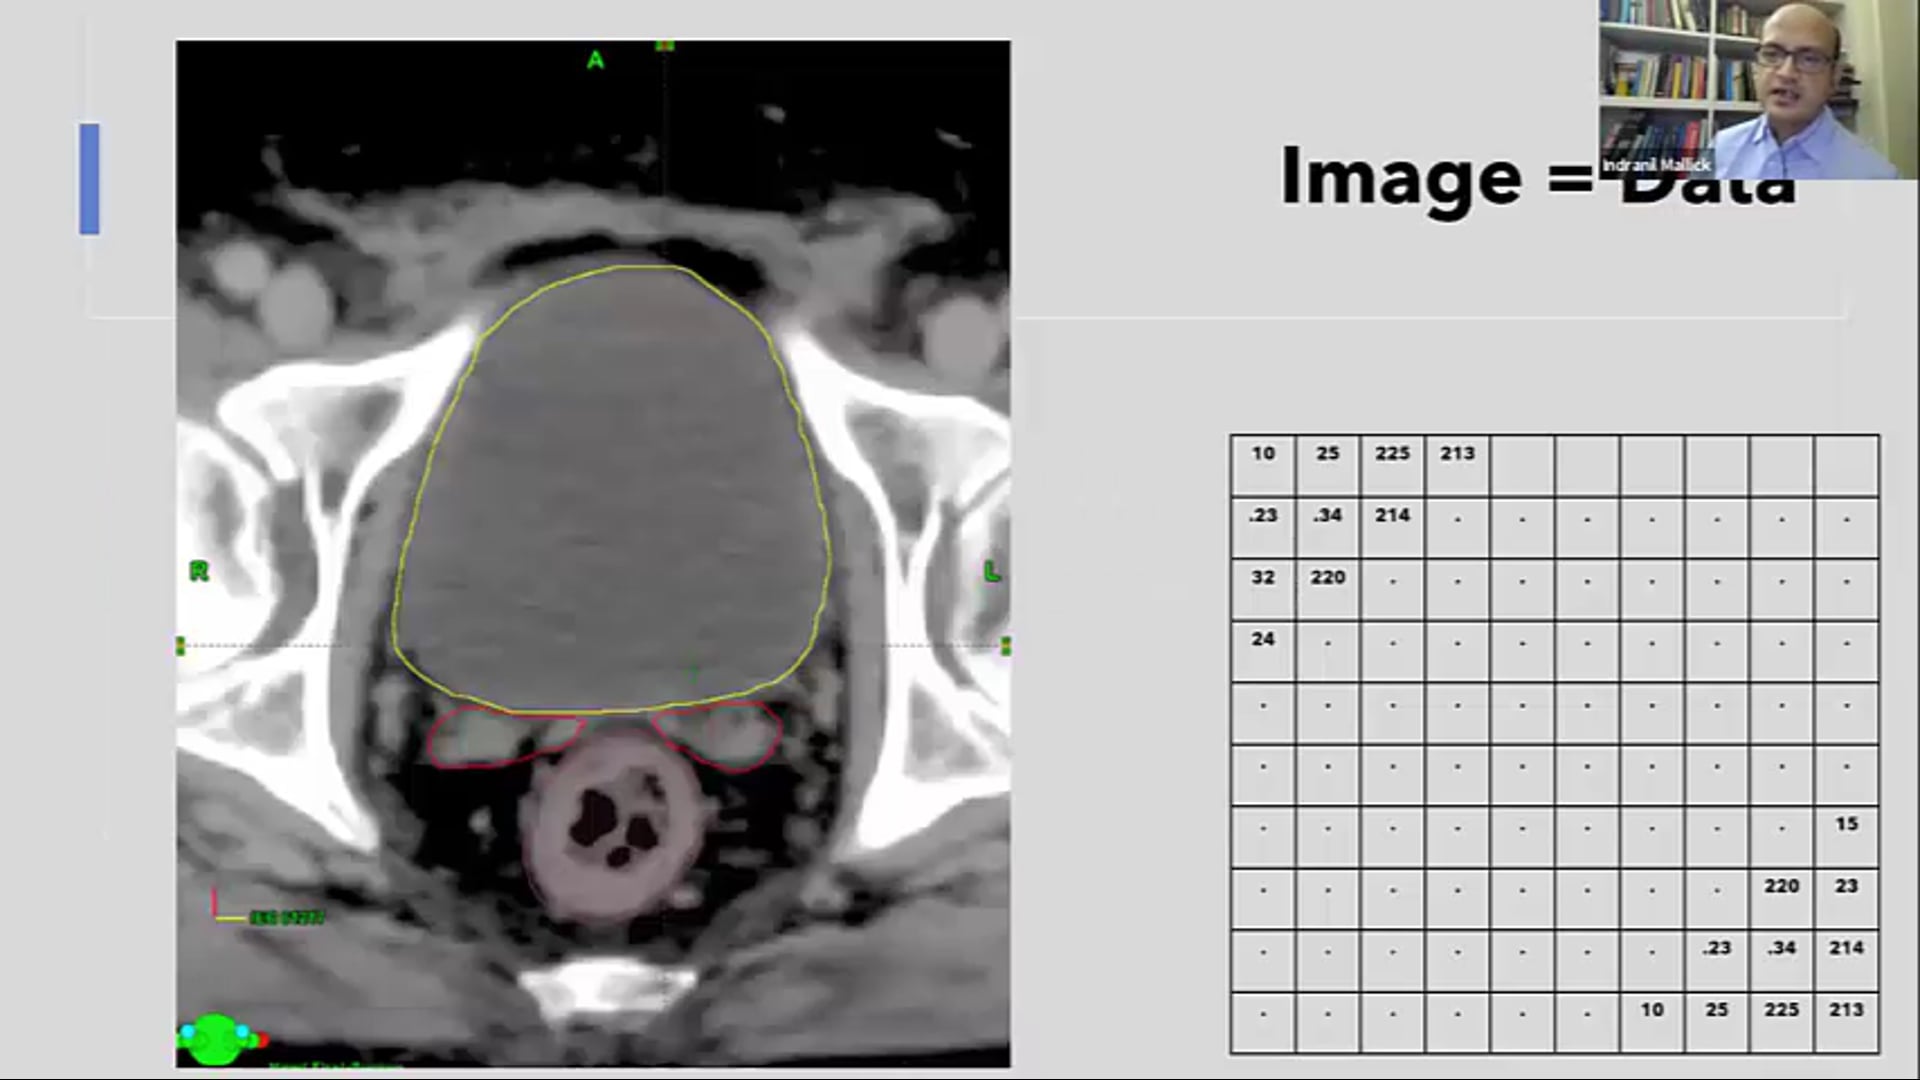

03/04/21 - Dr. Indranil Mallick - Data Science Machine Learning - GU India

Data Science ad Machine Learning in treatment planning- GU and GI cancers, DS/ML learning problems, AI segmentation, automated treatment planning, clinical challenges,